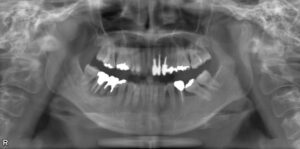

• 上下臼歯2本欠損症例

BEFORE AFTER 58歳女性/上下2本欠損/インプラント埋込手術 【治療内容】 左上第二小臼歯が欠損状態で、イン…